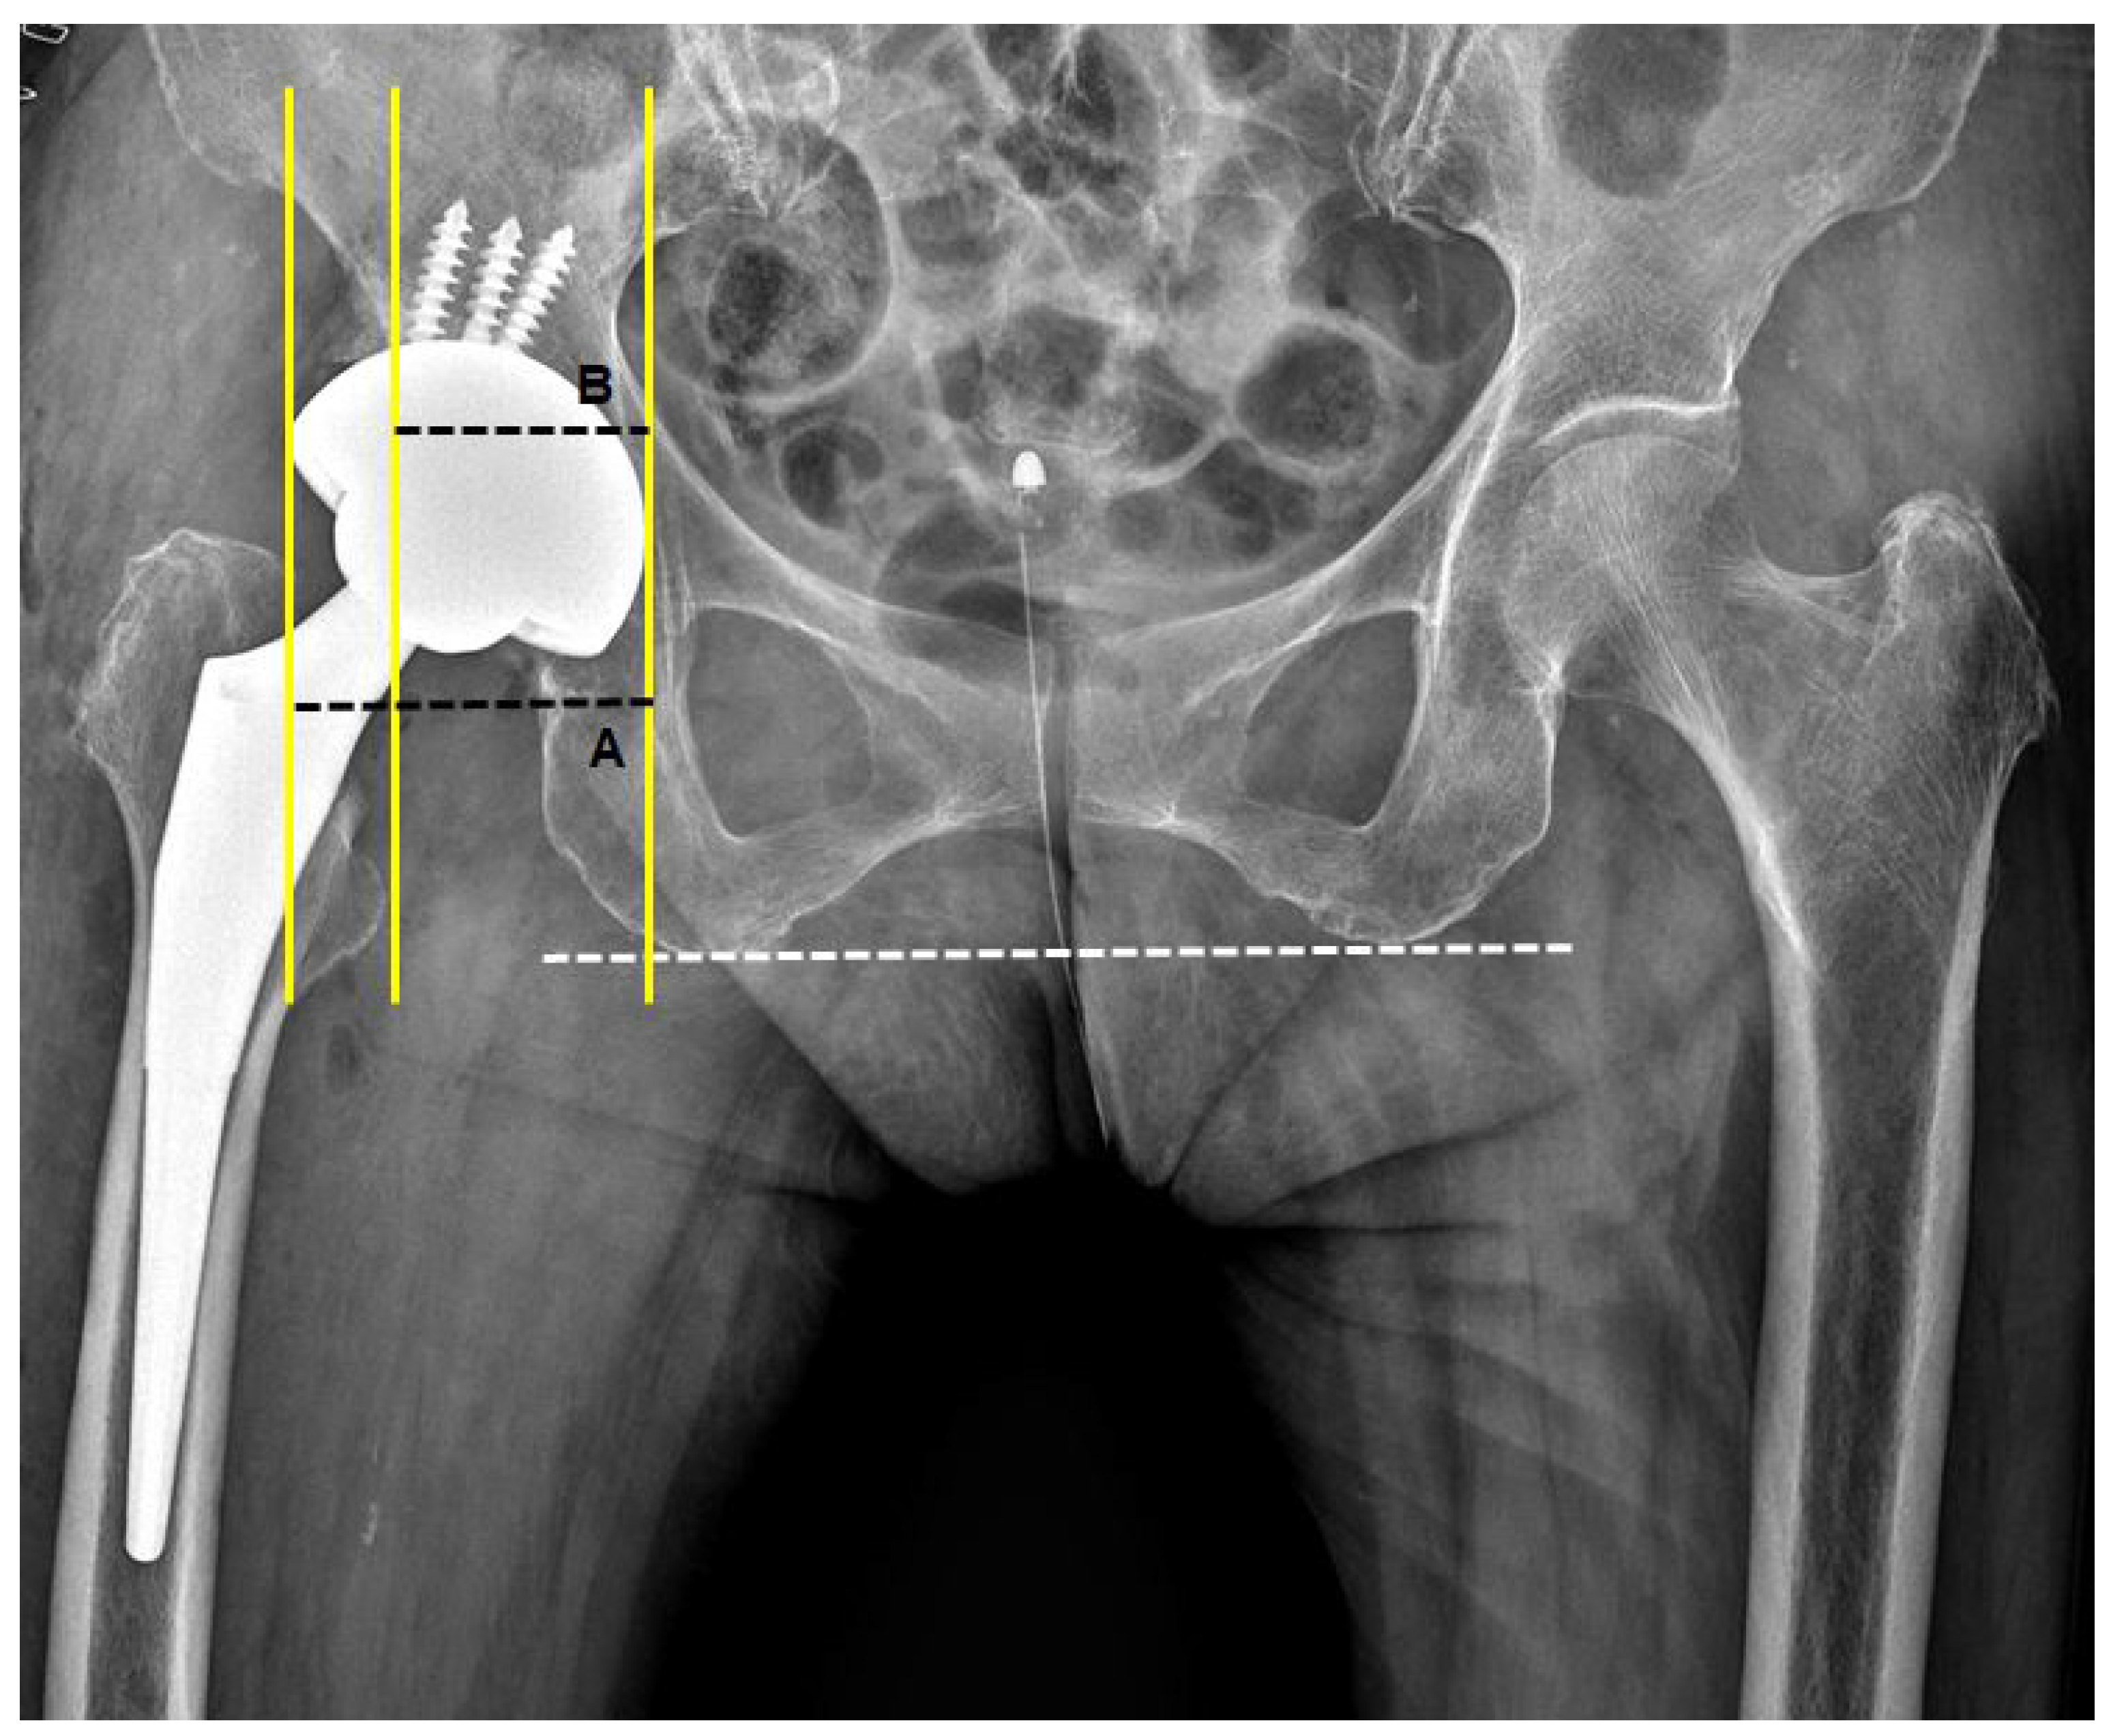

2.5. 2D-Based Measurement of Host Bone Coverage from Plain Radiographs of the Pelvis

3.2. Cup Position and Fixation